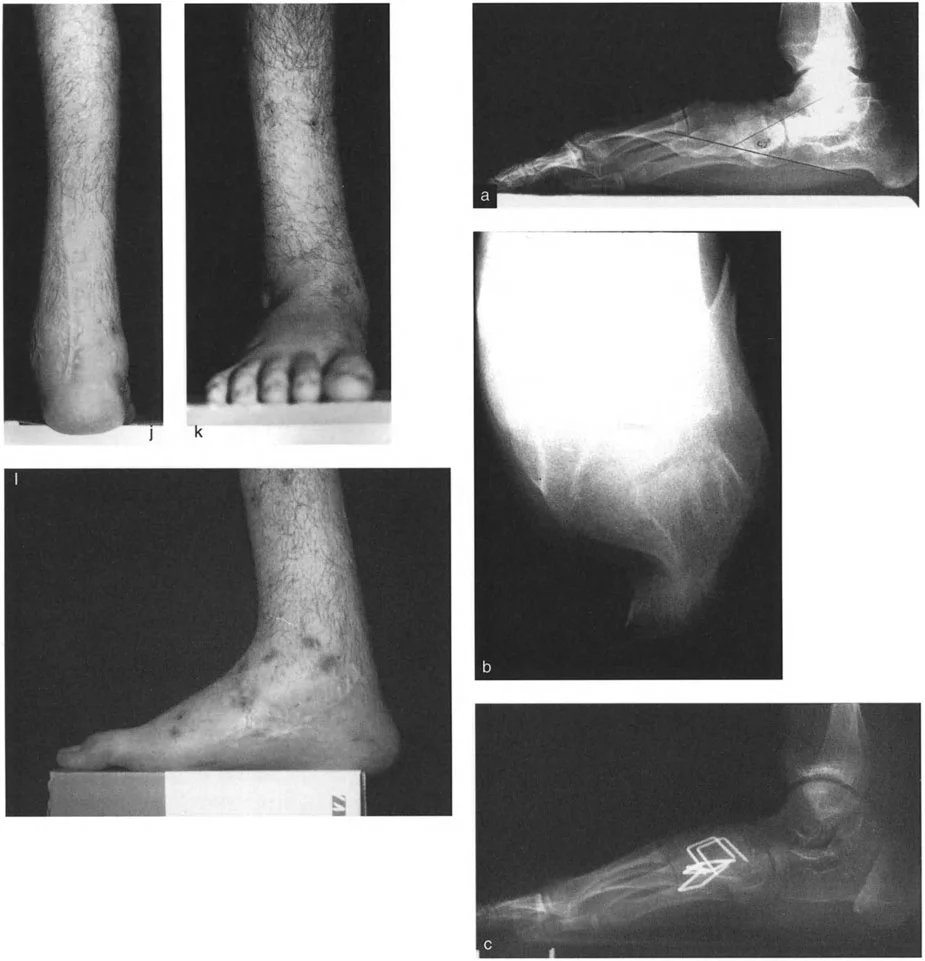

* الأشعة السينية الجانبية والامامية الخلفية للكاحل: تُظهر هذه الصور تفاصيل مفصل الكاحل نفسه، بما في ذلك زاوية القصبة الأمامية البعيدة (ADTA) وزاوية القصبة الوحشية البعيدة (LDTA)، وهي زوايا حاسمة لتحديد التشوه في المستويين الأمامي والسهمي.

* منظر سولتزمان (Saltzman View): هذا المنظر الإشعاعي الخاص يتم الحصول عليه بزاوية 20 درجة لقياس محاذاة عظم العقب (Calcaneus) بالنسبة لقصبة الساق، وهو أمر بالغ الأهمية لتقييم تعويضات القدم الخلفية.

صورة طبية: الاستاذ الدكتور محمد هطيف: دليل شامل لتشوهات قصبة الساق البعيدة والكاحل في صنعاء